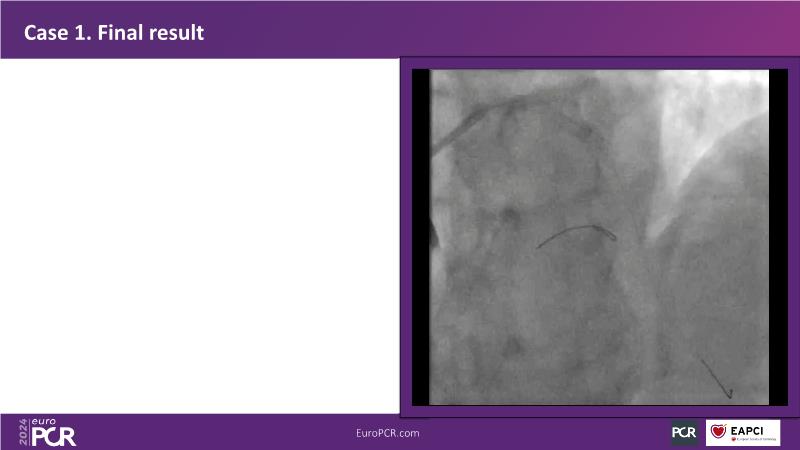

Don't miss this session for expert guidance on preparing and managing complex lesions. Gain insights into choosing the right tools, including microcatheters and balloons, for optimal treatment outcomes. Explore the innovative features of flagship devices for complex PCI, and Pronavi microcatheter and Alveo HP CTO balloon to treat complex CTO lesions. Learn about the safety and efficacy of the Wedge NC scoring balloon, the importance of using POT dedicated balloons in POT and DOT techniques, and get updated tips and tricks from ongoing clinical practices.

- To gain insights on Pronavi microcatheter and Alveo HP CTO balloon to treat complex CTO lesions, understand the safety and efficacy of lesion preparation with Wedge NC scoring balloon and the significance of using POT dedicated balloon in POT and DOT technique